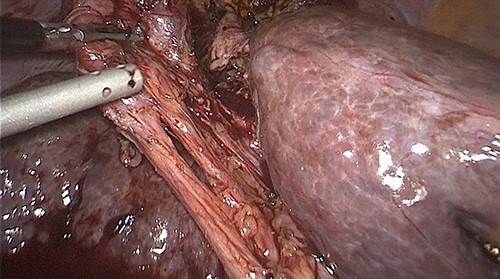

Prior to the surgical protocol, prophylactic antibiotics (ceftriaxone 1 g and metronidazole 500 mg) were administered during anesthetic induction. Three trocars were placed to perform the surgical procedure, one 11 mm supraumbilical (optical) and two 5 mm in the epigastrium and in the right upper quadrant. Pneumoperitoneum was induced with closed technique and the patient was placed in the reverse Trendelenburg position to begin the procedure. Inside the abdominal cavity, we observed the gallbladder adhered to the diaphragm (Fig. 2). The gallbladder was dissected, leaving the fundus of the gallbladder attached to the diaphragm (Fig. 3), the pleura and its movements were not appreciated, and lung tissue was not identified through the orifice. We could see a thick inflammatory tissue sealing the defect. Two giant stones were removed from the gallbladder’s fundus (Fig. 4) and the gallbladder was dissected antegrade. Cystic artery and duct were identified using Strasberg’s critical view of safety (Fig. 5). One distal and two proximal staples were placed in the cystic duct and cut, as well as a distal and one proximal staple in the cystic artery to cut as well. Later the gallbladder and stones were removed. Before ending the procedure, a drain was placed into the surgical wound, hemostasis was checked, and trocars were removed under direct vision. Finally, the fascia was closed with a 1–0 absorbable suture and the skin is closed with a 4–0 suture. There was no complications nor side effects in the mediate and immediate postoperatory.

Fundus of the gallbladder adhered to the diaphragm after dissection.